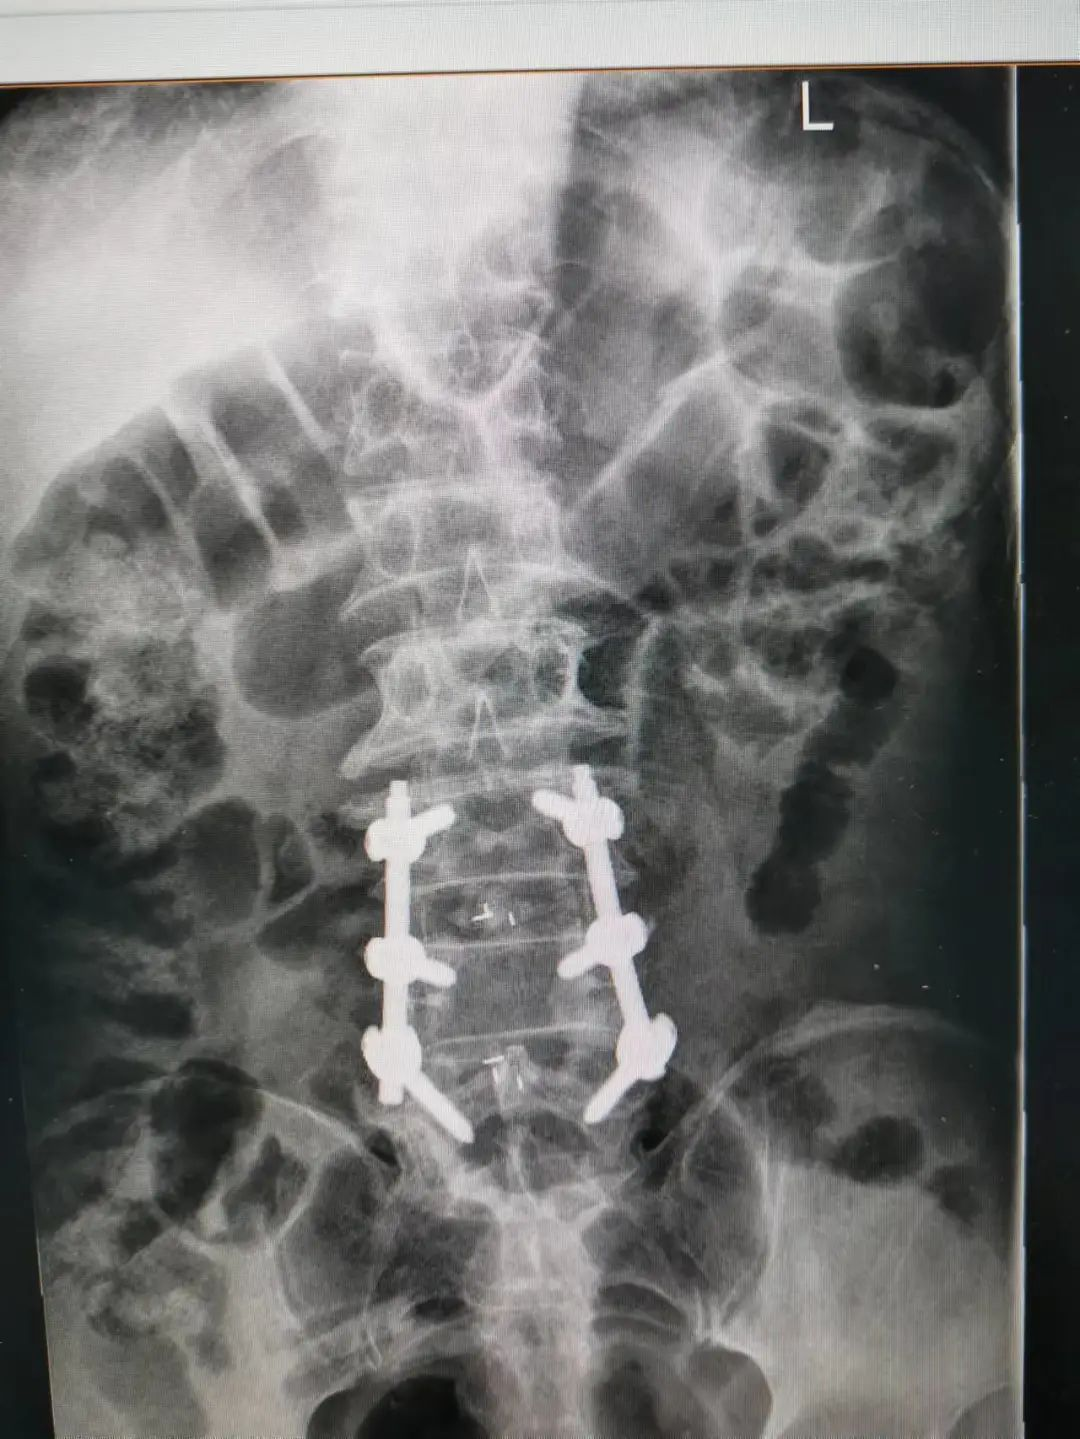

楊先生術(shù)后拍片

由于楊先生的病情嚴重,需住院治療。楊先生入院后,瀘州市中醫(yī)醫(yī)院骨傷二科科主任楊陳一制定了手術(shù)計劃,決定脊髓型頸椎病的手術(shù)從前路切開減壓,頸3/4 、頸4/5、 頸5/6、 頸6/7椎間盤切除,椎間融合,鋼板內(nèi)固定術(shù)手術(shù),而腰椎管狹窄癥經(jīng)后路切開減壓,腰3/4、腰4/5椎同盤動除,椎間融合、釘棒系統(tǒng)內(nèi)固定術(shù)。